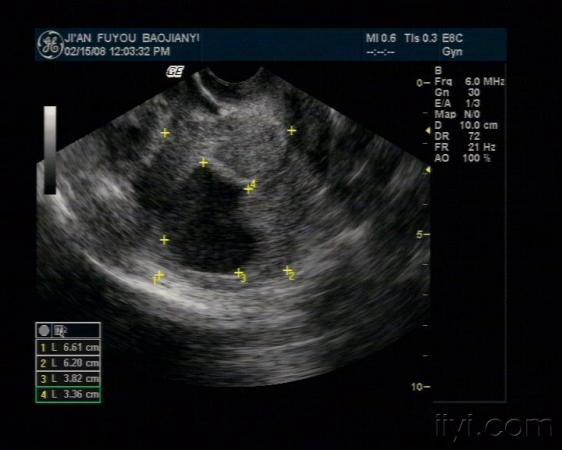

子宫位置:后位,大小约66*68*62mm,轮廓清晰,形态正常,肌层回声均匀。宫腔内见38*34mm暗区,其内见大量光点。

右侧附件区见混合回声光团,形态不规则,边界不清,内见类孕囊结构,大小47*27mm,见胎儿及原始心血管搏动,头臀长30mm。子宫直肠窝见液性暗区,最大厚径为21mm。

左侧附件区未见明显肿块回声。

1. 右侧附件区混合性包块--宫外孕

2. 盆腔积液

3. 宫内无回声区,考虑宫腔积血